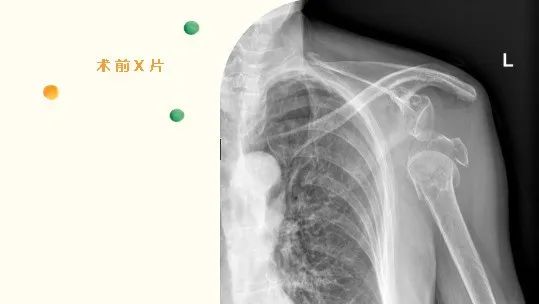

2022年6月,82岁的刁奶奶,因“摔伤致左肩部疼痛伴活动受限2+小时”入住我院骨伤科。入院后,骨伤科许锦涛主治医师通过详细的查体及相关辅助检查,诊断刁奶奶为“1.骨质疏松伴左肱骨近端粉碎性骨折2.左肩关节脱位”。

经过周密的术前准备,张成勇主任团队邀请四川省人民医院卢冰主任现场指导,顺利完成了手术,术中成功置入左侧反置式人工全肩关节假体,术后复查左肩DR,见假体位置良好,并在术后对病人进行康复训练。术后刁奶奶感疼痛明显减轻,正逐步康复锻炼,肩关节功能持续好转。